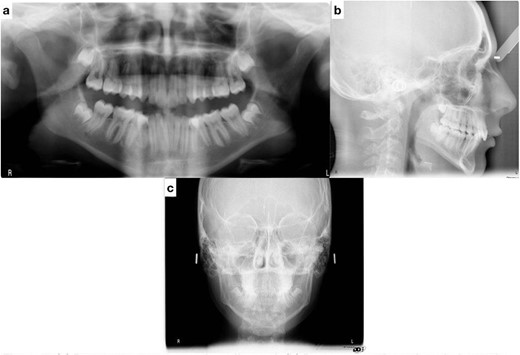

Lateral cephalometric radiograph analysis showed a mild mandibular deficiency and high mandibular plane angle, retroclined maxillary incisors and proclined mandibular incisors (Fig. 3b). Panoramic radiography showed impacted third molars; rocky mountain analysis on the posterior-anterior cephalometric radiograph showed a narrow maxilla in the transverse dimension (Fig. 3c).

(a) Pretreatment panoramic radiograph; (b) pretreatment lateral cephalometric radiograph; (c) pretreatment posterior-anterior cephalometric radiograph.